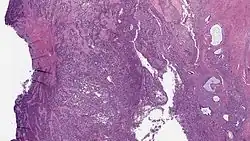

| Micrograph of a low-grade endometrial stromal sarcoma. H&E stain. | |

Low-grade endometrial stromal sarcoma consists of cells resembling normal proliferative phase endometrium, but with infiltration or vascular invasion. These behave less[3] aggressively, sometimes metastasizing, with cancer stage the best predictor of survival. The cells express estrogen/progesterone-receptors.